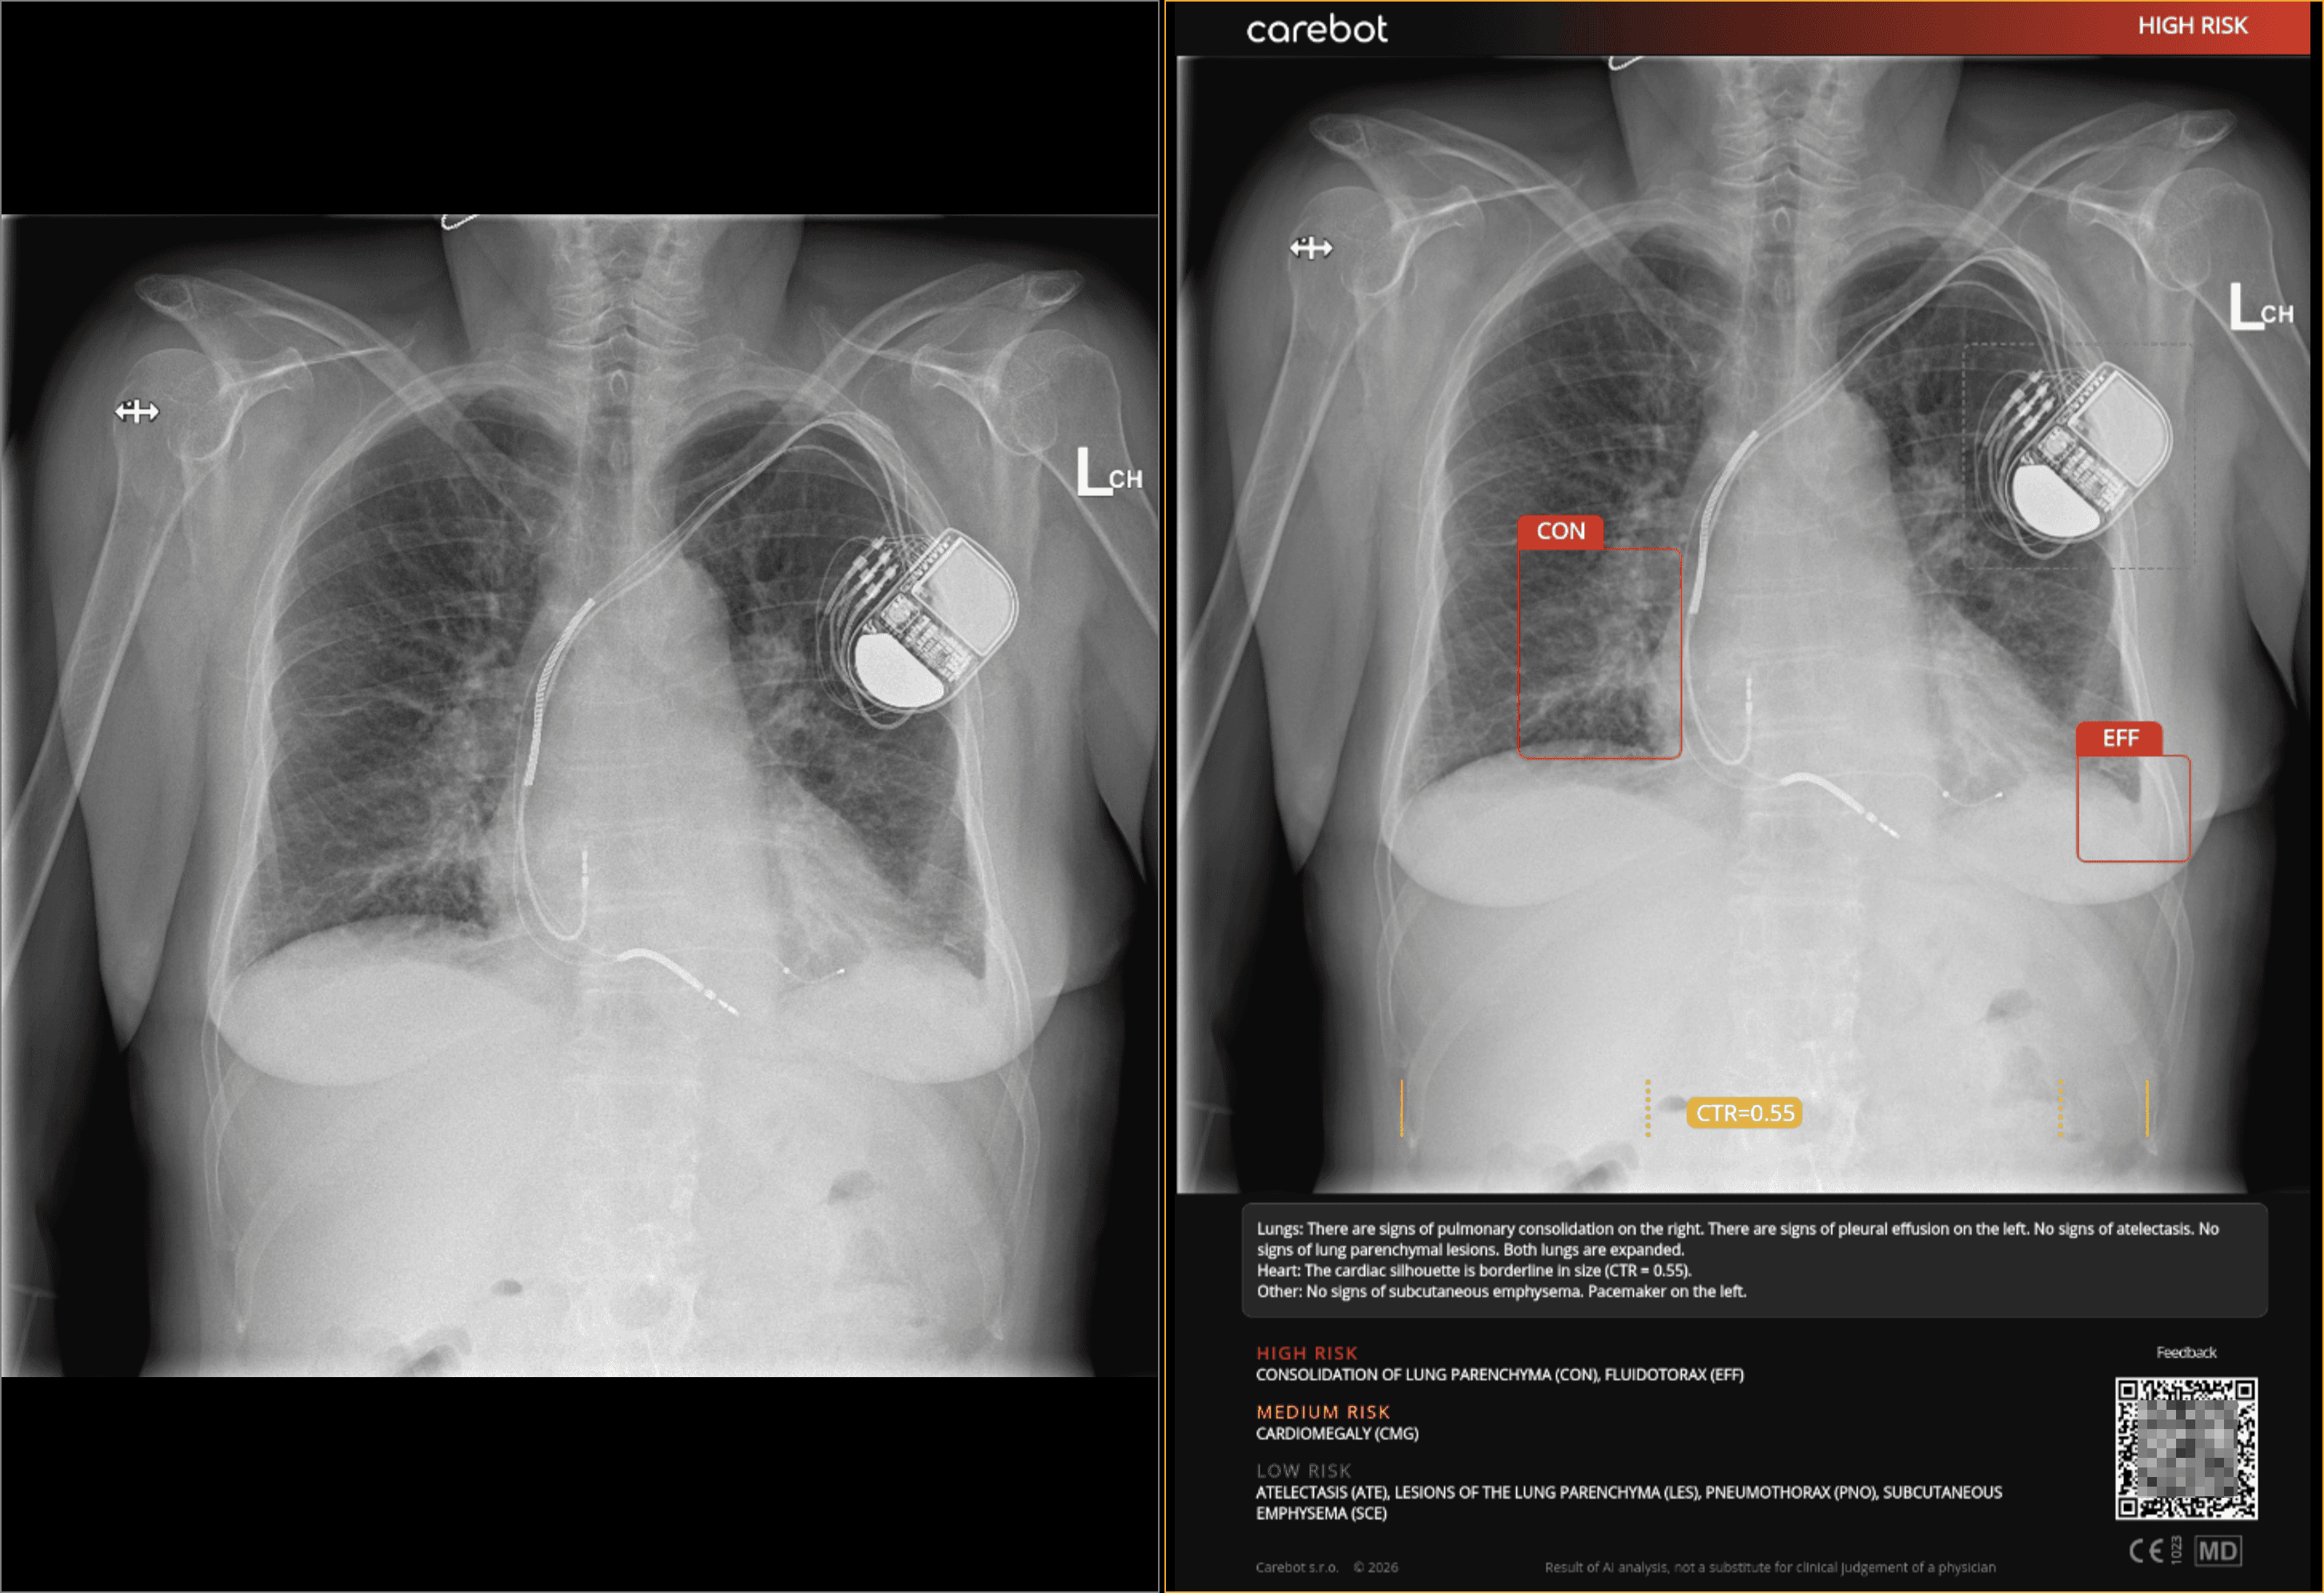

Carebot has released a new version of Carebot AI CXR that adds automatic detection and localization of common external devices on chest X-ray. The update supports identification of endotracheal tubes, central venous catheters, pleural and mediastinal drains, and pacemakers.

The detected devices are integrated directly into Carebot’s reporting workflow alongside existing pathology outputs. This allows radiologists and clinicians to review AI findings in one place and use them as part of routine reporting without changing their established workflows.